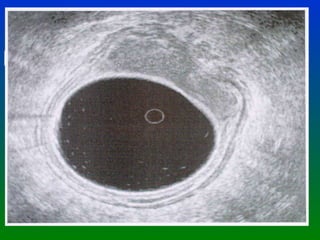

CANCER DE RECTO DIAGNOSTICO ANNALS OF ONCOLOGY SUPLEMENTO OCT. 2002 El Ultrasonido endorrectal es la mejor herramienta Para evaluar la invasión tumoral en la pared rectal. Con un elevado % de sensibilidad y especificidad. UT 1 Invasión hasta la muscularis mucosa UT 2 Invasión hasta la muscularis propia PT 1 Confinado a la grasa submucosa * En estas condiciones la mejor elección es una  Excisión local

CANCER DE RECTODIAGNOSTICO ANNALS OF ONCOLOGY SUPLEMENTO OCT. 2002 El Ultrasonido endorrectal es la mejor herramienta Para evaluar la invasión tumoral en la pared rectal. Con un elevado % de sensibilidad y especificidad. UT 1 Invasión hasta la muscularis mucosa UT 2 Invasión hasta la muscularis propia PT 1 Confinado a la grasa submucosa * En estas condiciones la mejor elección es una Excisión local